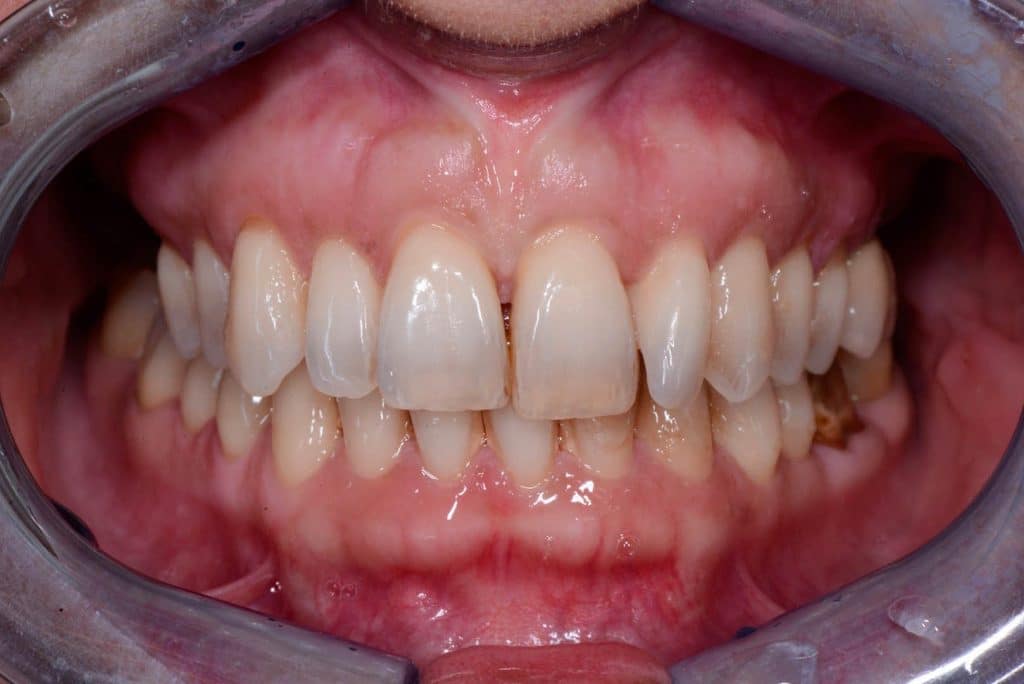

one week follow-up